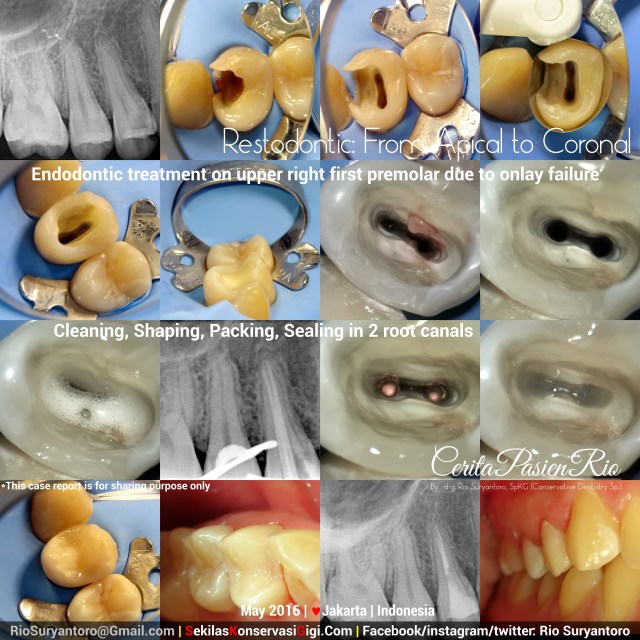

Restodontic: From Apical to Coronal

This time, i got referral from well known oral surgeon in Jakarta, Dr. Dede Bachtiar SpBM., to do an Endodontic Treatment on Upper right first premolar with Irreversible pulpitis.

At radiographic image, the caries has extended into the pulp. Clinical examination also showed this condition, with class II origin.

At first, i did access preparation and rebuild up the mesial wall in order to create a 4 walled cavity access by composite resin (Filtek_Bulkfill fron 3M) with help of Omni Matrix (ultradent).

Cleaning and shaping was done with ProtaperNext (Dentsply) and Natrium hypochlorite 5,24%.. after obturation with gutta percha, the orifices were coronally sealed with Low_shrinkage_stress flowable composite (filtek_bulkfill flowable from 3M) and packable composite (filtek Z350XT from 3M). Xray examination with Vistaray 7.1 at 70kV, 2mA, 0,06s showed intact margin, and homogeneous body of restoration and tooth structure..